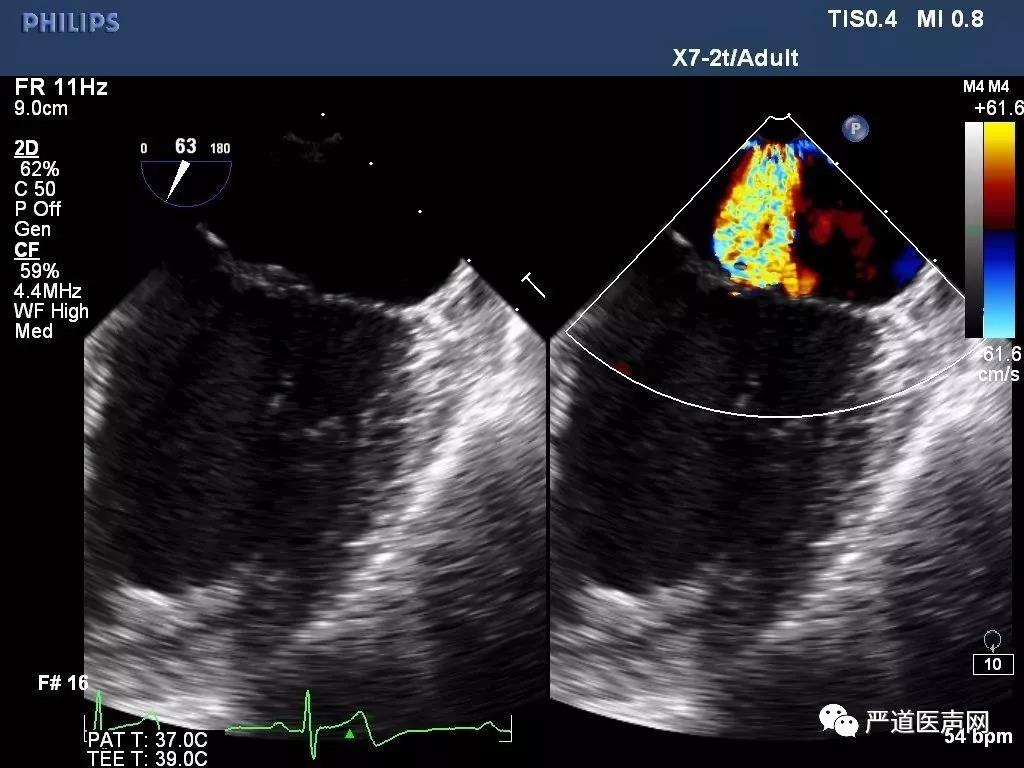

高齡老年男性患者,超聲提示二尖瓣后瓣及前瓣脫垂伴重度反流,有明確臨床癥狀,反復(fù)出現(xiàn)心衰臨床表現(xiàn),并具有多種合并癥。經(jīng)過討論,該患者行傳統(tǒng)外科手術(shù)風(fēng)險較高,選擇性微創(chuàng)ValveClamp治療。圍手術(shù)期經(jīng)食道超聲(TEE)確認二尖瓣退行性病變,前瓣后瓣A2/P2脫垂伴重度反流,脫垂區(qū)域?qū)挾?2mm,手術(shù)采用全麻左前胸3cm微創(chuàng)切口,通過心尖如路16F血管鞘完成,無需體外循環(huán)及心臟停跳,在TEE引導(dǎo)下準確將上海捍宇醫(yī)療創(chuàng)新研發(fā)的ValveClamp準確釋放于A2/P2脫垂區(qū)域,行介入緣對緣(edge-to-edge)修復(fù),整個手術(shù)過程順利,植入時間僅25分鐘,無明顯失血,術(shù)后TEE提示二尖瓣反流即刻為極微量,二尖瓣雙孔化形成,二尖瓣平均跨瓣壓差僅為2mmHg,瓣口無狹窄,臨床效果滿意。

圖1: TEE提示二尖瓣重度反流